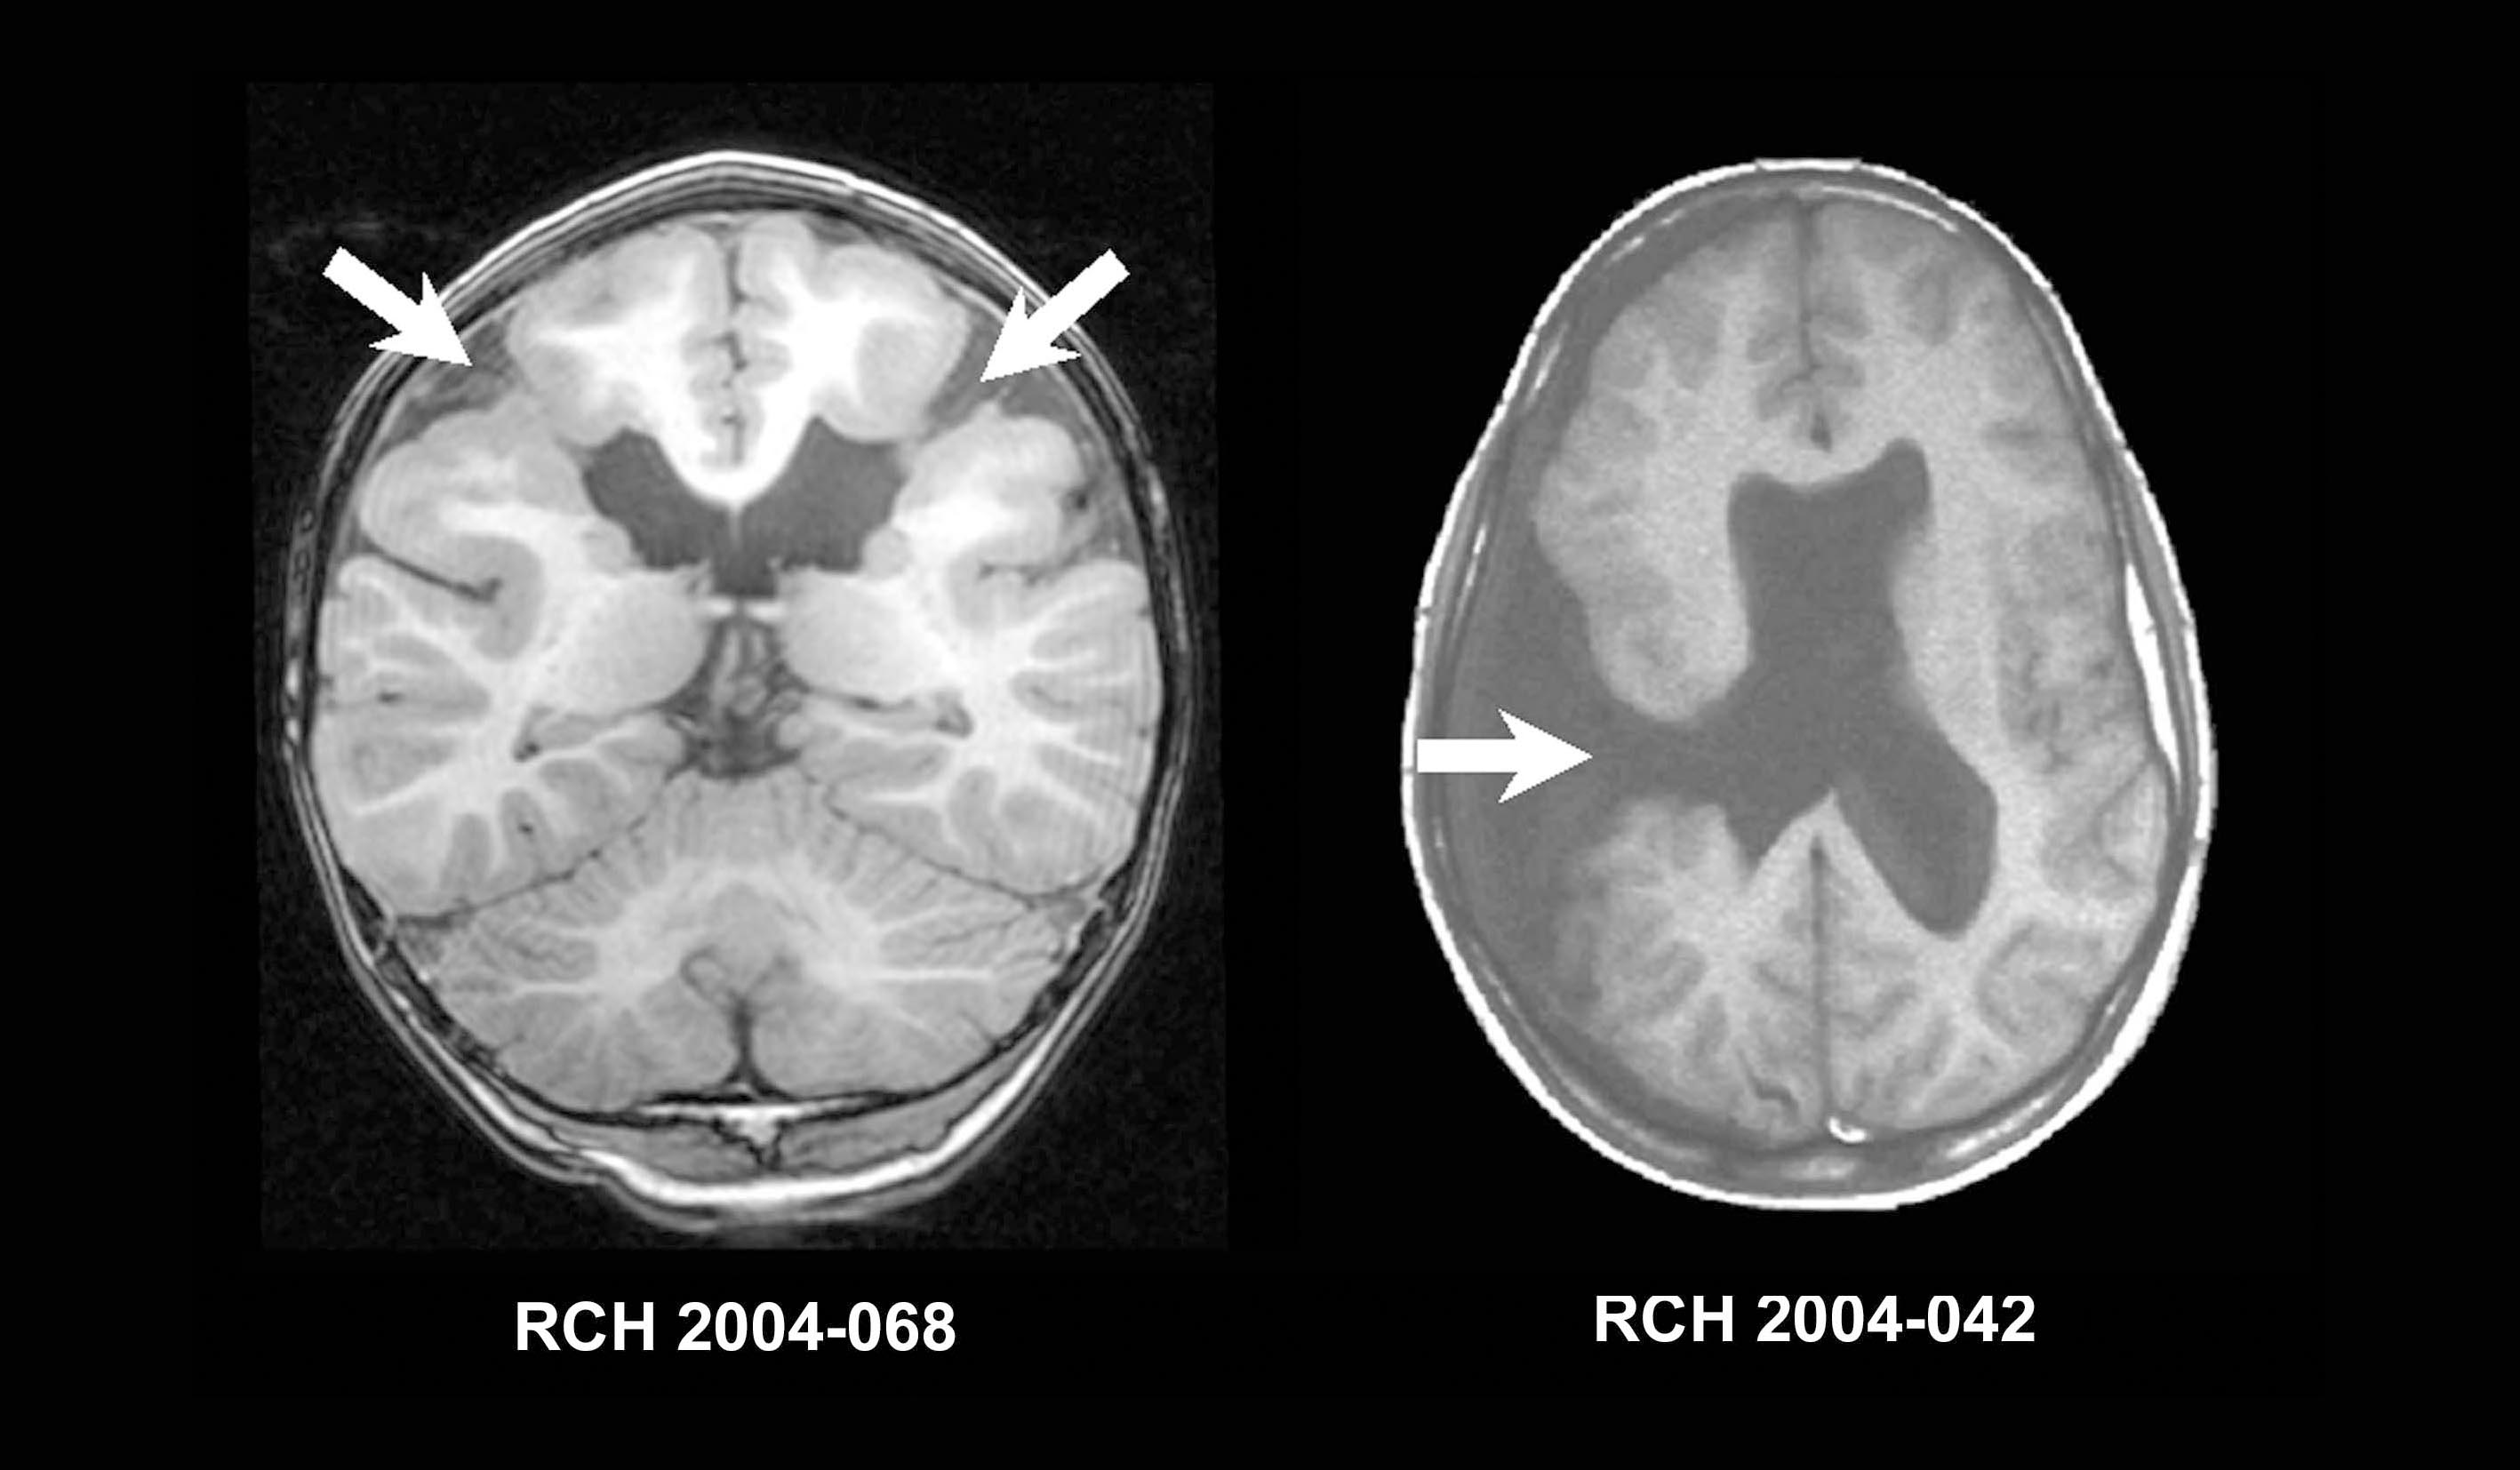

A esquizencefalia é uma malformação congênita que se caracteriza por fenda unilateral ou bilateral nos hemisférios cerebrais.

Essa fenda normalmente se estende do córtex à região periventricular. Sua causa pode ser genética ou algum fator intercorrente da gravidez. Como por exemplo a isquemia cerebral fetal em decorrência de problemas circulatórios da mãe.